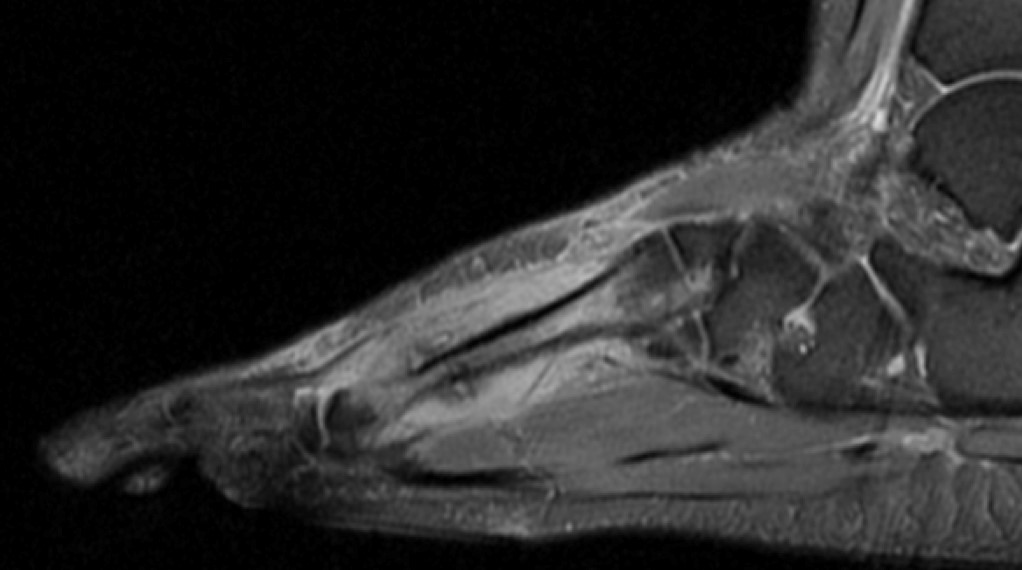

– Co, jakie kości, łamiemy najczęściej z powodu przeciążenia?

– Biegacze najczęściej łamią kości śródstopia, przede wszystkim drugą, trzecia i czwartą. Nieco rzadziej zdarzają się złamania kości w podudziu, piszczelowej i strzałkowej, rzadko złamania szyjki kości udowej i miednicy, które są najniebezpieczniejsze i wymagają najbardziej radykalnego leczenia, łącznie z operacją.